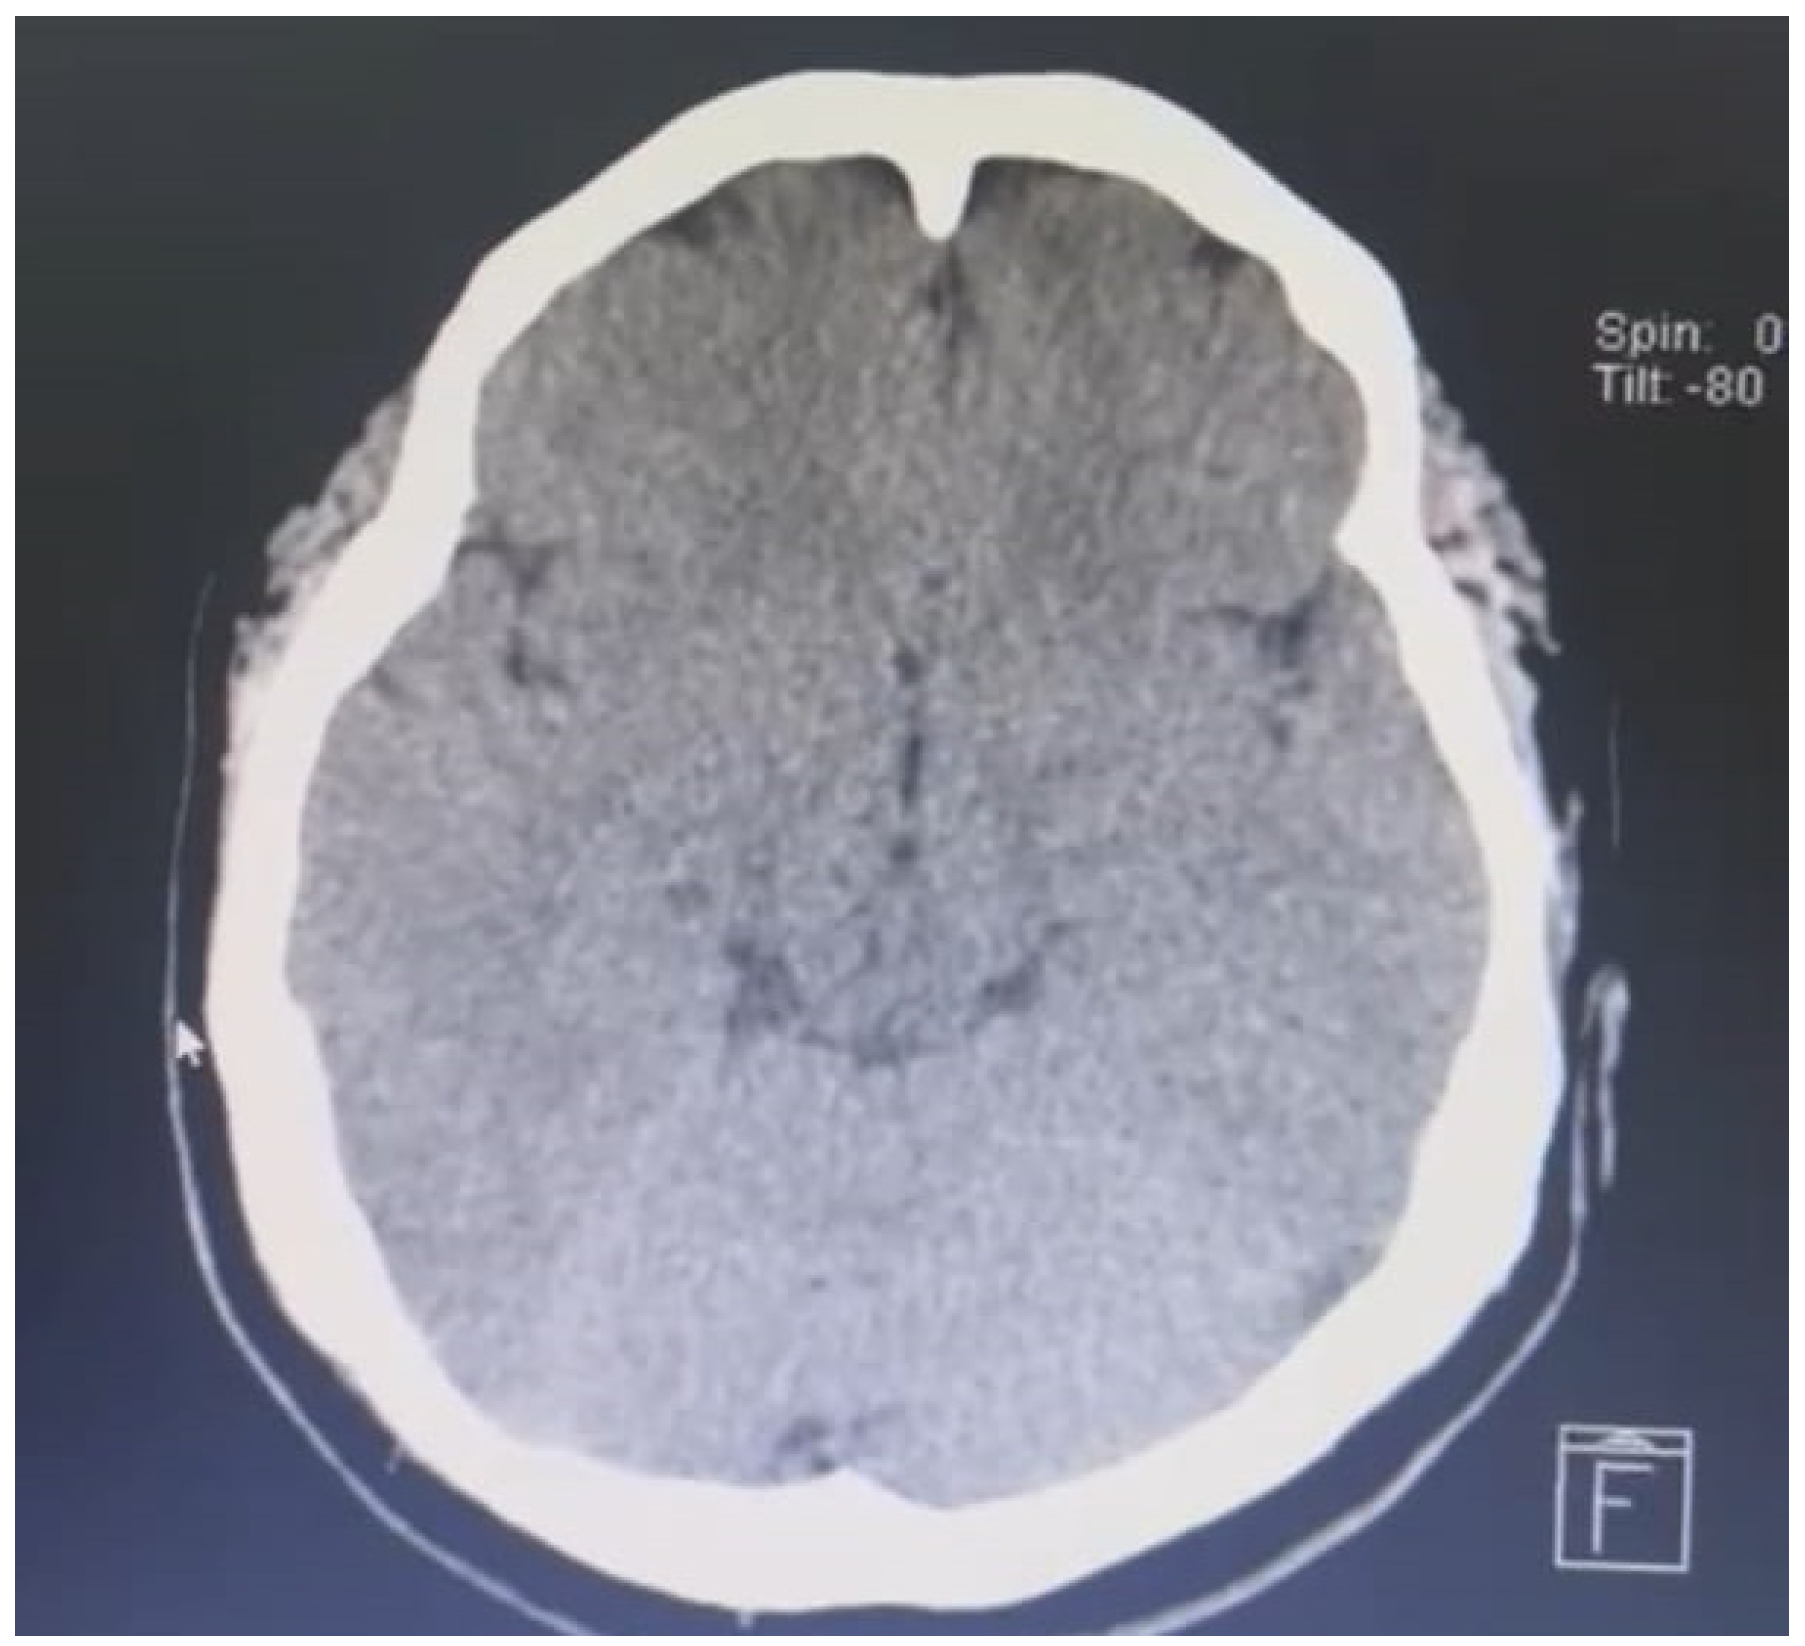

In the laboratories carried out on admission, only a thrombocytopenia of 135,000 was observed. It is then considered to carry out a brain angioresonance which showed the presence of thrombosis of both transverse venous sinuses in the right at the proximal level and in the left at the distal level.

Figure 2. Angioresonance performed on the patient.